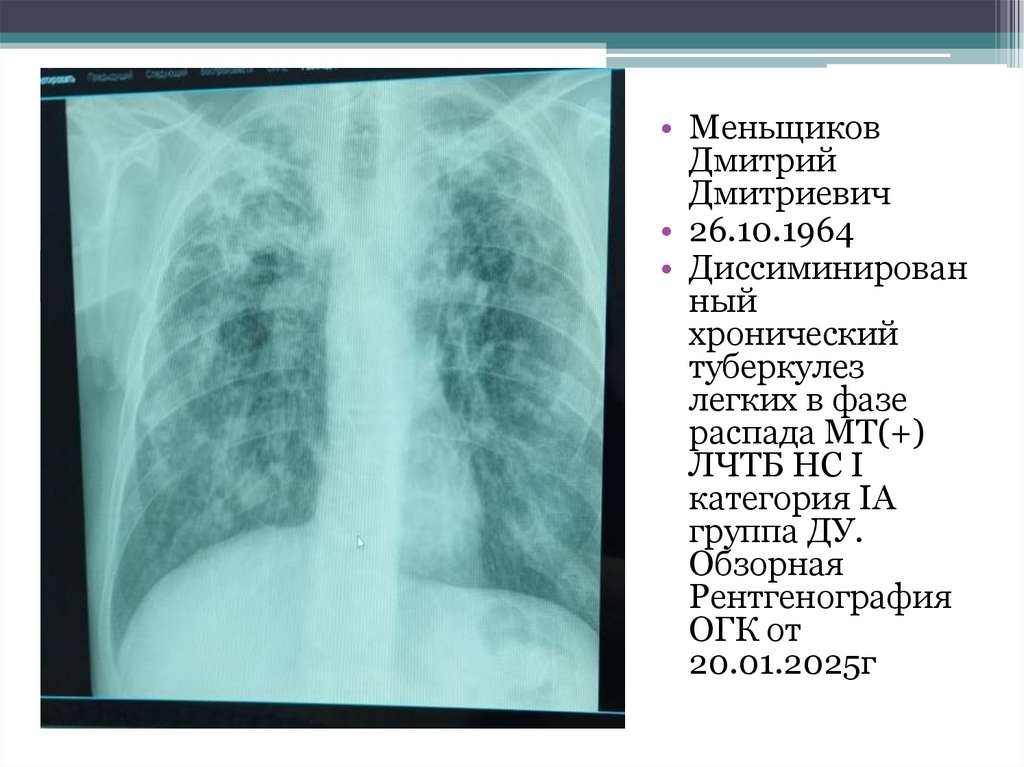

13. Ларионов Вадим Викторович 29.03.1980 г.р. Диагноз:  Инфильтративный туберкулез легких в фазе распада и обсеменения МТ+ ЛЧТБ Тип

• Ларионов Вадим Викторович

29.03.1980 г.р.

Диагноз:

Инфильтративный туберкулез легких в фазе

распада и обсеменения МТ+ ЛЧТБ Тип

"Рецидив" проф 1 А группа ДУ.

• Ларионов Вадим Викторович 29.03.1980 г.р. Диагноз:

• Инфильтративный туберкулез легких в фазе распада и обсеменения МТ+ ЛЧТБ Тип

"Рецидив" проф 1 А группа ДУ. Рентген снимки в начале лечения ЦВКК от 26.11.2024г